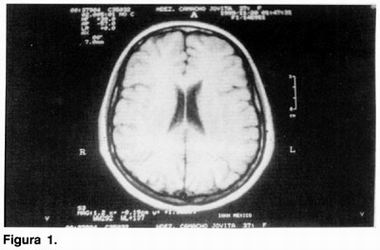

A su ingreso, se realiza BH, QS, ES, PFH, PF (tiroides, cortisol y prolactina), EEG y P-300 resultando dentro de límites normales. La IRM mostró asimetría en el sistema ventricular por mayor talla ventricular izquierda con datos sugestivos de atrofía subcortical de hemisferio izquierdo (figuras 1 y 2).

La paciente que presentamos cumple con los criterios clínicos y por imagen para catalogarla como síndrome de hemiparkinsonismo-hemiatrofía. La paciente presenta de inicio hemiparkinsonismo, derecho, se documenta hemiatrofia corporal derecha de al menos 2 cm como se describe previamente, 2 y las imágenes por RM muestran una franca asimetría ventricular por dilatación del ventrículo lateral izquierdo. Los datos de asimetría hemicorporal son objetivos y confiables debido a que en la paciente que es diestra se esperaría una asimetría hemicorporal izquierda, dato que no presento, y por el contrario, el hemicuerpo pr edominante en la paciente (derecho), es el que se encuentra más afectado. La respuesta favorable que encontro en nuestra paciente con farmacoterapia utilizada para el Parkinson idiopático va de acuerdo con lo anteriormente descrito en que el síndrome tiene una base patogénica similar al PI, pero con substratos genéticos diferentes debido a la respuesta al tratamiento y a la evolución más prolongada que se ha descrito.